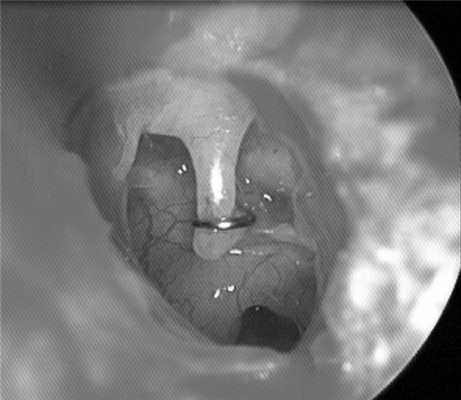

В дальнейшем в этой области развился рубцовый процесс, что привело к сращению жировой ткани с лентикулярным отростком и вызвало его смещение во внутреннее ухо. При ревизии осмотру была доступна только петля протеза, а его ножка полностью скрыта в рубце (рис. 4). Рисунок 4. Интраоперационное фото. Смещение стапедиального протеза во внутренне ухо.

Протез был удален, после чего пациентка уже на операционном столе отметила значительное уменьшение головокружения. Спайки в области овального окна были рассечены, лентикулярный отросток наковальни отведен латерально. В имеющееся отверстие в нише овального окна был установлен титановый протез К-пистон минимального размера 4,0 мм (рис. 5). Рисунок 5. Интраоперационное фото. Установлен протез К-пистон 4,0 мм. Послеоперационный период протекал спокойно. Пациентка была повторно консультирована сурдологом и отоневрологом. Отмечен регресс горизонтального спонтанного нистагма вправо. Выписана с улучшением на 7-е сутки после операции.